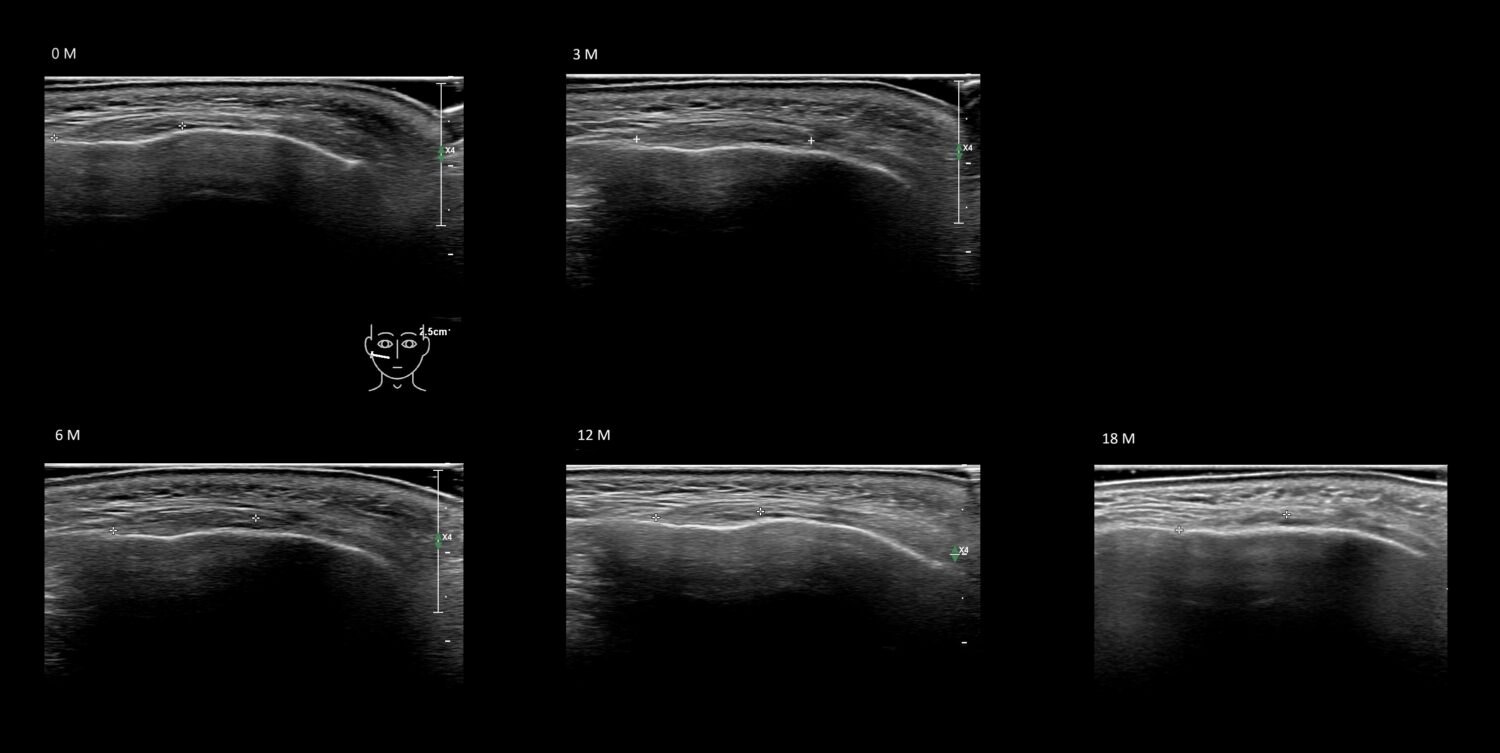

Fillers

Draw in the second image below where the fillers are located. To check if your answer is correct, swipe the first image to the right.